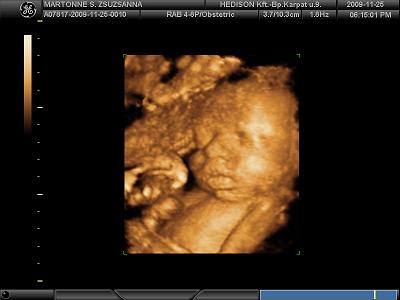

Köszönöm a képeket!!!!!

Tenci jól eltalálta, tényleg Jolie-s szája van Tominak!

És ha még Brad Pittre is fog hasonlítani............!!!!!!!!